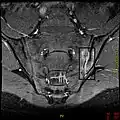

T1-weighted MRI with fat suppression after administration of gadolinium contrast showing sacroiliitis in a person with ankylosing spondylitis